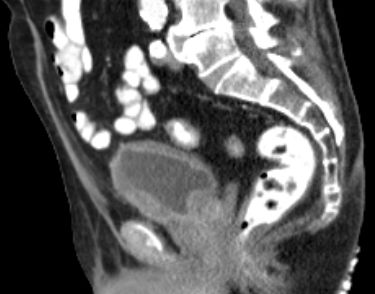

| Becken-Rezidiv | 54-jährige Frau nach radikaler Zystektomie und Anlage eines Ileumconduits wegen eines Plattenepithelkarzinoms der Harnblase vor 8 Monaten. Jetzt Verdacht eines Abszesses an der linken Beckenwand. Anlage eines Transversostomas und Drainage, später transvaginale Drainageeinlage. Jetzt Tumorfreilegung, Nekroseausräumung, Drainage. Histologie: Plattenepithelkarzinom. Destruktion des Beckenknochens links mit Einbruch ins Acetabulums. | ||